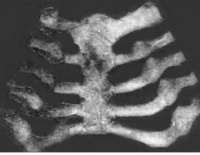

佝偻病胸骨x线表现

肋骨外翻,就是宝宝的肋骨下缘翘起来。这个需要有经验的医生才能作出准确的判断。很多宝宝也存在不同程度肋骨外翻的。

其他的骨骼变形有鸡胸、漏斗胸、X型腿、O型腿、肋串珠、手镯和脚镯,这些是比较严重的佝偻病才会出现的。现在已经很少见了。

胸部软骨串珠状;肋软沟;肋下缘外翻;鸡胸;漏斗胸。